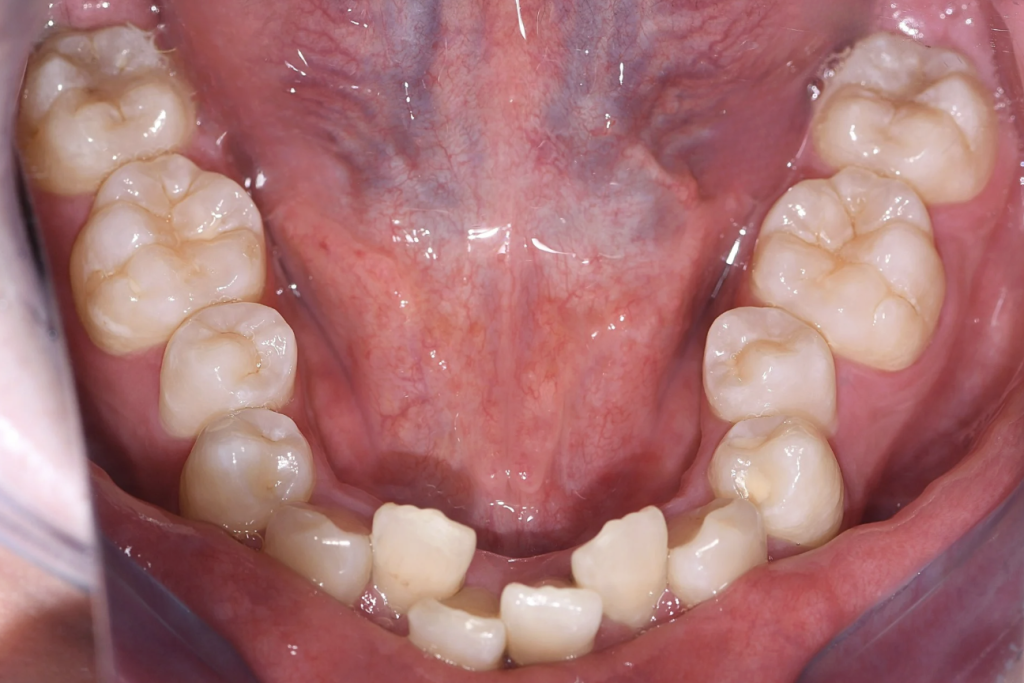

永久歯に大きさに対し、歯を並べるスペース(顎)が小さく、

上下ともに狭窄歯列、下顎前歯には叢生(歯のガタつき)、上顎前歯の突出感が認められました。